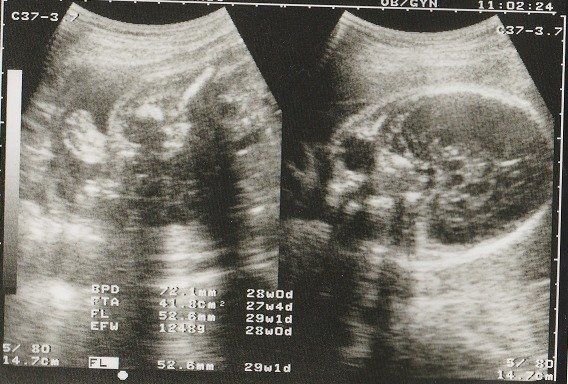

妊娠29週目のエコー写真 お母さんの体にむくみなどが出てくる時期

赤ちゃんの眼球が写っています。このころ、おなかのなかで赤ちゃんも寝たり起きたりしているそうです。

この時期になると、手足のむくみが気になるようになりました。

妊娠30週目のエコー写真 お母さんも大きくなる時期

赤ちゃんも順調に育っていますが、お母さんの体重も増え気味に…。「あまり体重が増えると管理入院ですよ」と、看護婦さんに釘を刺されました。

妊娠32週目のエコー写真 おなかもぱんぱんです。

AC(おなかの周囲の長さ)などから、赤ちゃんの推定体重を計算するようです。赤ちゃんのおなかも大きくなっていますが、お母さんのおなかもぱんぱんです。